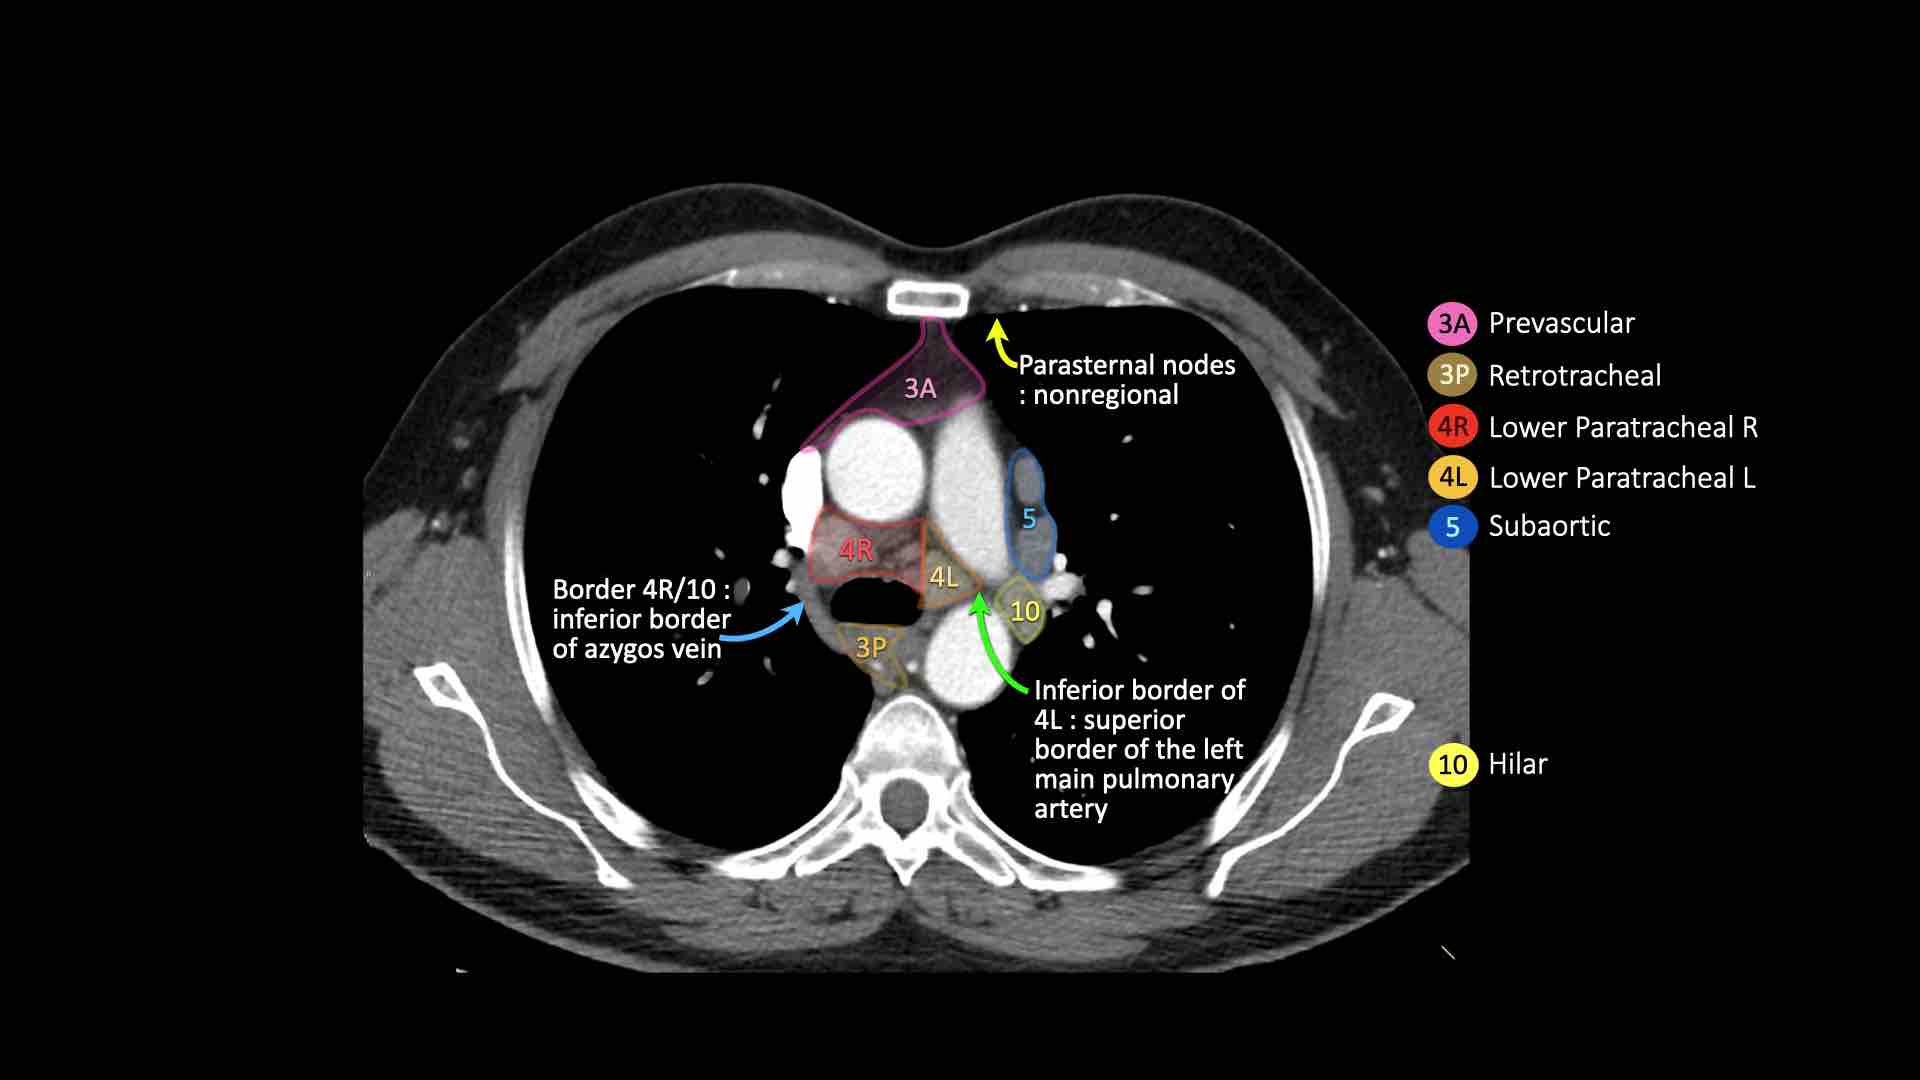

4R.Cạnh khí quản dưới

Từ điểm giao nhau giữa bờ dưới tĩnh mạch vô danh (tĩnh mạch tay đầu trái) với khí quản đến bờ dưới tĩnh mạch đơn.

Hạch nhóm 4R trải dài từ bờ bên phải đến bờ bên trái của khí quản.

4L.Cạnh khí quản dưới

Từ bờ trên của quai động mạch chủ đến bờ trên của động mạch phổi trái.

5. Dưới động mạch chủ

Các hạch này nằm trong cửa sổ phế động mạch (AP window), ở phía ngoài dây chằng động mạch.

Các hạch này không nằm giữa động mạch chủ và thân động mạch phổi mà nằm ở phía ngoài các mạch máu này.

10. Hạch rốn phổi

Bao gồm các hạch tiếp giáp với phế quản gốc và các mạch máu rốn phổi.

Bên phải, trải dài từ bờ dưới tĩnh mạch đơn đến vùng gian thùy.

Bên trái, từ bờ trên động mạch phổi đến vùng gian thùy.

4R. Hạch cạnh khí quản dưới bên phải

Ranh giới trên: giao điểm của bờ dưới tĩnh mạch vô danh (tĩnh mạch tay đầu trái) với khí quản.

Ranh giới dưới: bờ dưới tĩnh mạch đơn.

Hạch nhóm 4R trải dài đến bờ bên trái của khí quản.

4L. Hạch cạnh khí quản dưới bên trái

Hạch nhóm 4L là các hạch cạnh khí quản dưới nằm bên trái bờ trái của khí quản, giữa đường nằm ngang tiếp tuyến với bờ trên quai động mạch chủ và đường tiếp tuyến với bờ trên động mạch phổi trái.

Nhóm này bao gồm các hạch cạnh khí quản nằm ở phía trong dây chằng động mạch.

Hạch nhóm 5 (cửa sổ phế động mạch) nằm ở phía ngoài dây chằng động mạch.

Bên trái là hình ảnh ngay trên mức thân động mạch phổi, cho thấy các hạch cạnh khí quản dưới bên trái và bên phải.

Ngoài ra còn có các hạch nhóm 3 và nhóm 5.

Bên trái là hình ảnh ở mức phần dưới khí quản, ngay trên carina.

Bên trái khí quản là các hạch 4L.

Lưu ý rằng các hạch 4L này nằm giữa thân động mạch phổi và động mạch chủ, nhưng không nằm trong cửa sổ phế động mạch, vì chúng nằm ở phía trong dây chằng động mạch.

Hạch nằm bên ngoài thân động mạch phổi là hạch nhóm 5.